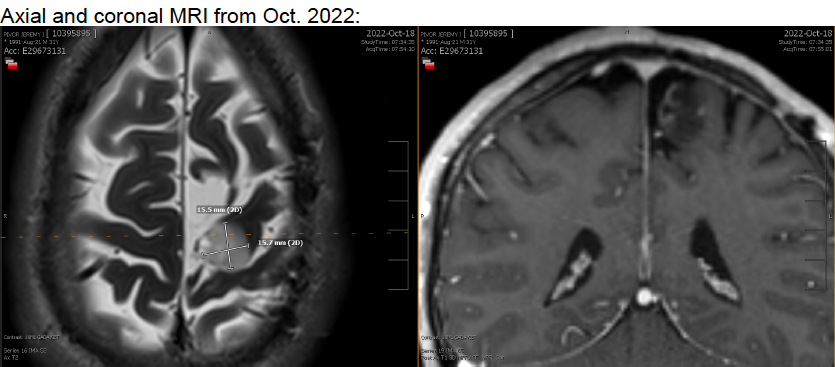

The balance between quantity and quality is what always influences my treatment decisions, and is ultimately why I went for an aggressive surgery with a highly recommended and skilled surgeon. And as you know, she was able to remove the entire tumor nodule! See the below MRI scans from before my surgery and during the surgery.